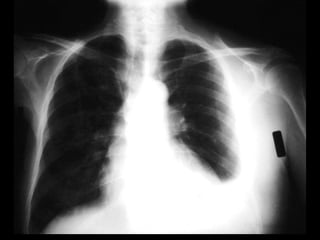

Chest Radiography

• Effusions of more than 175 mL are usually

apparent as blunting of the costophrenic angle on

upright posteroanterior chest radiographs. On

supine chest radiographs, which are commonly

used in the intensive care setting, moderate to

large pleural effusions may appear as a

homogenous increase in density spread over the

lower lung fields. Apparent elevation of the

hemidiaphragm, lateral displacement of the dome

of the diaphragm, or increased distance between

the apparent left hemidiaphragm and the gastric

air bubble suggests subpulmonic effusions.